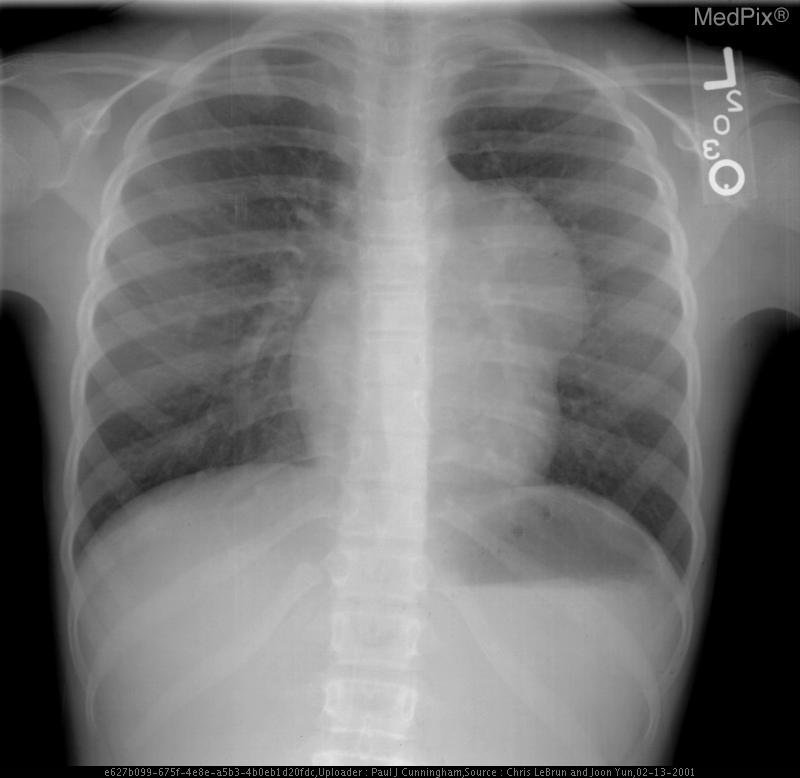

Mediastinal Teratoma

• Diagnosis: Mediastinal Mature Teratoma

1) Findings:

- Frontal chest radiograph, properly oriented: image-left = patient-right.

- Cardiac silhouette is mildly displaced toward the image-right (patient-left), suggesting mass effect from a mediastinal lesion.

- A well-circumscribed, rounded opacity occupies the image-left (patient-right) upper mediastinum, with smooth margins.

- The lesion shows heterogeneous internal density, including areas of relative lucency (suggesting fat) and opacity (possibly soft tissue or calcification).

- Lungs otherwise clear without focal consolidation or effusion.

- Bony thorax intact with no visible rib destruction or vertebral abnormality.

- Trachea slightly deviated toward image-right (patient-left), consistent with mild mediastinal shift.

- Diaphragms symmetric; cardiopericardial silhouette otherwise unremarkable except for mass effect.

2) Most likely diagnosis and why:

Anterior mediastinal teratoma. The well-defined, heterogeneous mass in the anterior mediastinum with soft tissue and possible fatty or calcific elements is characteristic of a mediastinal teratoma. Leftward (patient-left) cardiac displacement and tracheal shift support a space-occupying lesion in the anterior mediastinum. Context consistency: Consistent. The reported age (child) and sex (female) align with a known demographic pattern for benign mediastinal teratoma. Confidence: 90%.